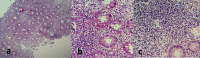

Figures